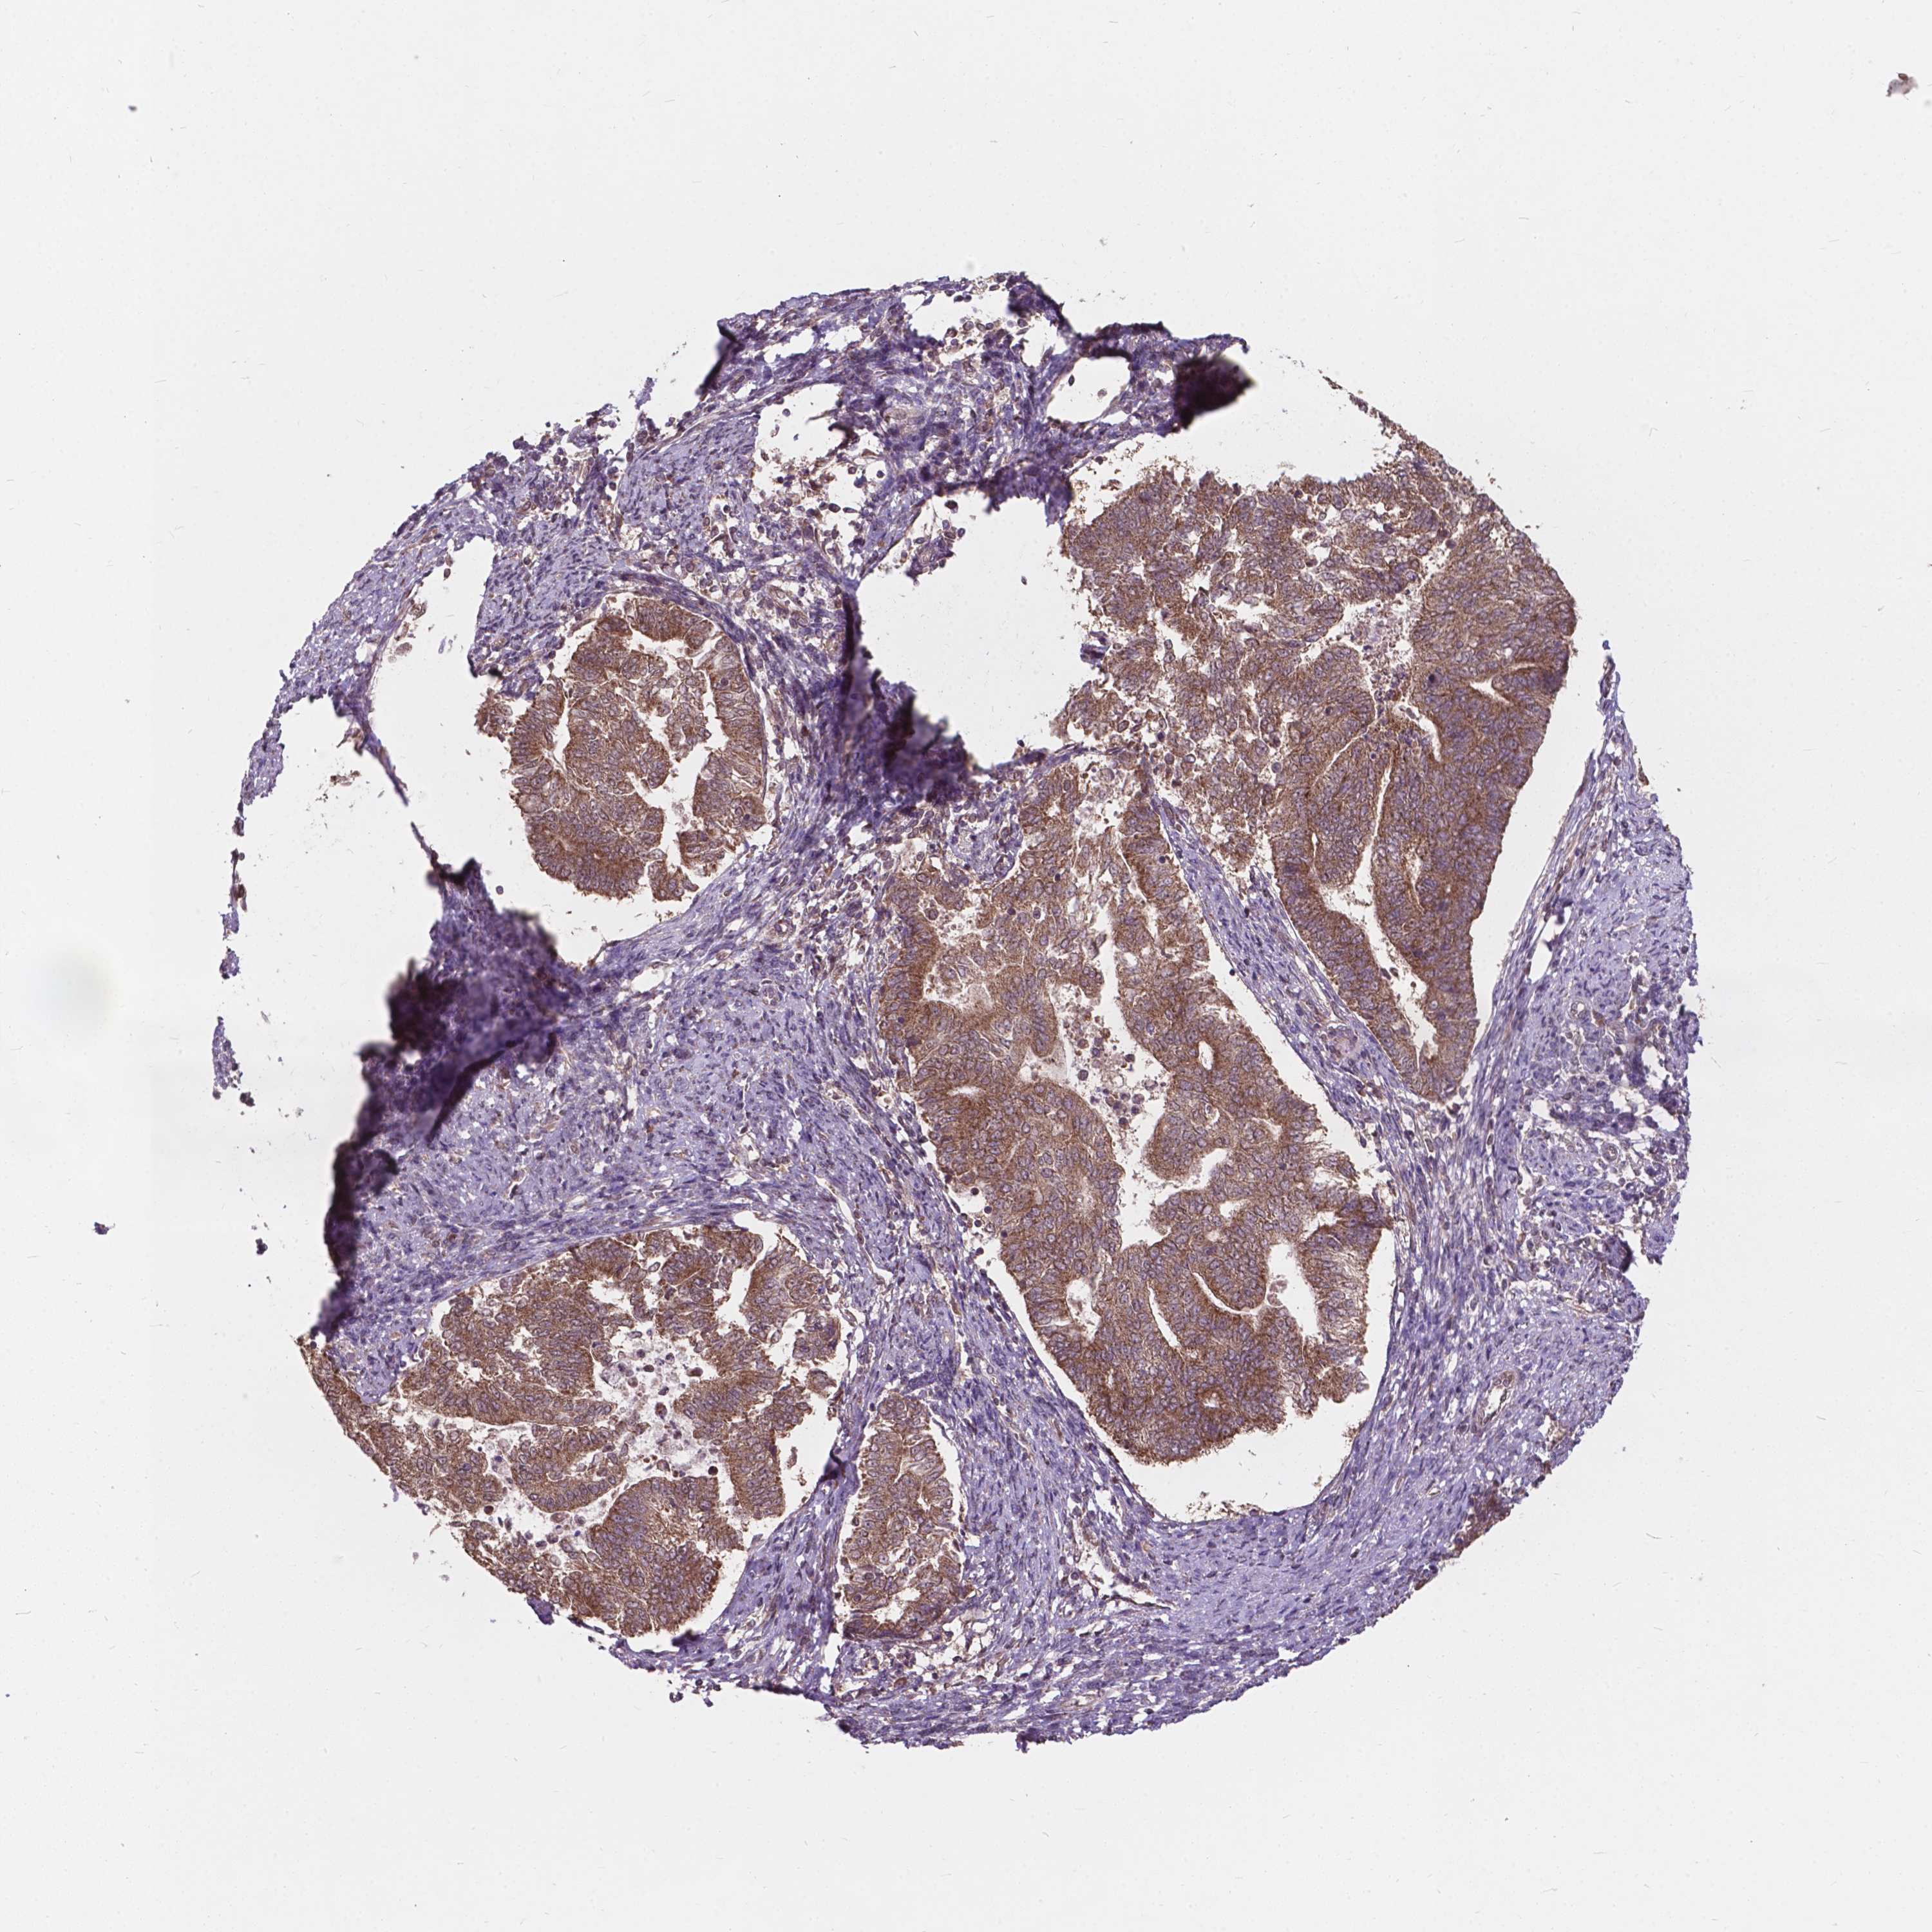

ENDOMETRIAL CANCER - Protein expressioni

A mouse-over function shows sample information and annotation data. Click on an image to view it in a full screen mode. Samples can be filtered based on level of antibody staining by selecting one or several of the following categories: high, medium, low and not detected. The assay and annotation is described here.

Note that samples used for immunohistochemistry by the Human Protein Atlas do not correspond to samples in the TCGA dataset.

Antibody stainingi

Antibody staining in the annotated cell types in the current human tissue is reported as not detected, low, medium, or high, based on conventional immunohistochemistry profiling in selected tissues. This score is based on the combination of the staining intensity and fraction of stained cells.

Each image is clickable and will lead to virtual microscopy that enables deeper exploration of all samples and also displays staining intensity scores, fraction scores and subcellular localization as well as patient and tissue information for each sample.

Antibody HPA066872

Staining

High

Medium

Low

Not detected

Intensity

Strong

Moderate

Weak

Negative

Quantity

>75%

75%-25%

<25%

None

Location

Nuclear

Cytoplasmic/membranous

Cytoplasmic/membranous,nuclear

Adenocarcinoma, NOS